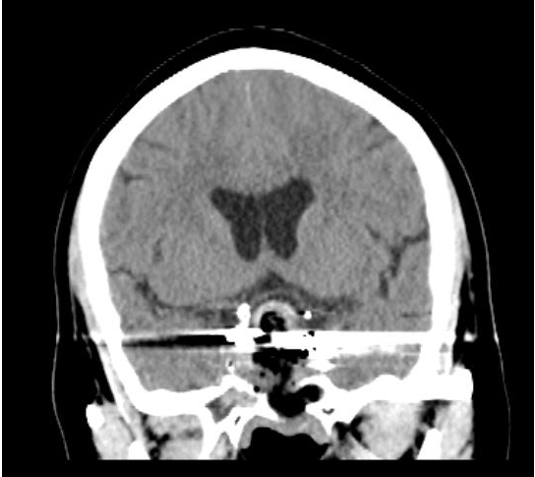

术前头部CT,提示鞍区肿瘤,累及鞍内鞍上